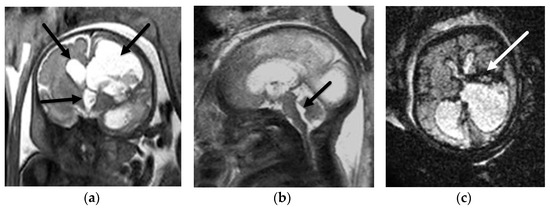

3.1.1. Aqueductal Stenosis

- Heaphy-Henault, K.; Guimaraes, C.; Mehollin-Ray, A.; Cassady, C.I.; Zhang, W.; Desai, N.K.; Paldino, M.J. Congenital aqueductal stenosis: Findings at fetal MRI that accurately predict a postnatal diagnosis. Am. J. Neuroradiol. 2018, 39, 942–948. [Google Scholar] [CrossRef] [PubMed] [Green Version]

- Kline-Fath, B.M.; Arroyo, M.S.; Calvo-Garcia, M.A.; Horn, P.S.; Thomas, C. Prenatal aqueduct stenosis: Association with rhombencephalosynapsis and neonatal outcome. Prenat. Diagn. 2018, 38, 1028–1034. [Google Scholar] [CrossRef] [PubMed]